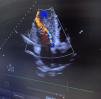

A 47-year-old woman with a past medical history of bicuspid aortopathy in her paternal grandfather; her parents died young in a traffic accident. Due to palpitations, the outpatient echocardiogram performed revealed the presence of a dilated ventricle with a left ventricular end-diastolic diameter of 71mm, indexed 3.4mm/m², left ventricular ejection fraction of 55–60%, in addition to a bicuspid aortic valve with fusion between the right and left coronary cusps that triggered severe aortic regurgitation (Fig. 2) with an aortic root of 40mm. A computed tomography scan was requested for preoperative study (Fig. 1), which was performed 3 weeks later, evidencing a Stanford/DeBakey type A aortic dissection I with an intimal flap at root level that extended longitudinally (Fig. 3) and spirally towards the left common iliac artery, involving the right brachiocephalic trunk without compromising its flow. In light of these findings, the patient was transferred to the cardiac intensive care unit for emergency surgery, undergoing David surgery with independent reimplantation of the brachiocephalic trunk.